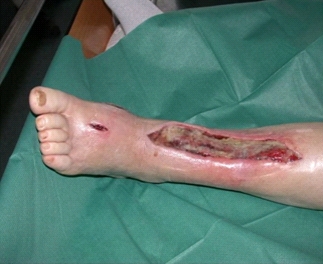

가스 괴저(Gas gangrene)

증상

열감

,

마찰음

환부 부종

환부 통증

환부의 분비물

관련질환

급성 신부전

파종혈관내응고

진료과

감염내과

응급의학과

정형외과